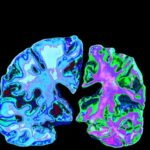

Neural therapy stimulates and regulates the autonomic nervous system, a vast electrical network within our body. This helps restore the body’s internal balance, eliminates negative effects on cells, and promotes normal cell function. Its positive effects on the nervous, circulatory, and lymphatic systems make it suitable for a wide variety of conditions.

With regulatory medicine, healing is achieved by ensuring the balanced physiological functioning of all organs and systems, taking into account the integrity of the body. Neural therapy is one of the most important tools of regulatory medicine.